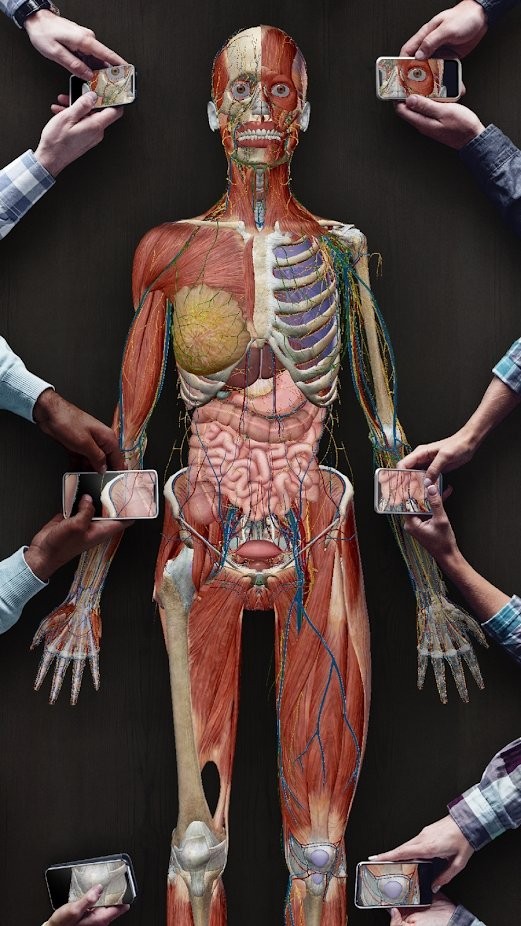

#2021人体解剖图谱 截图